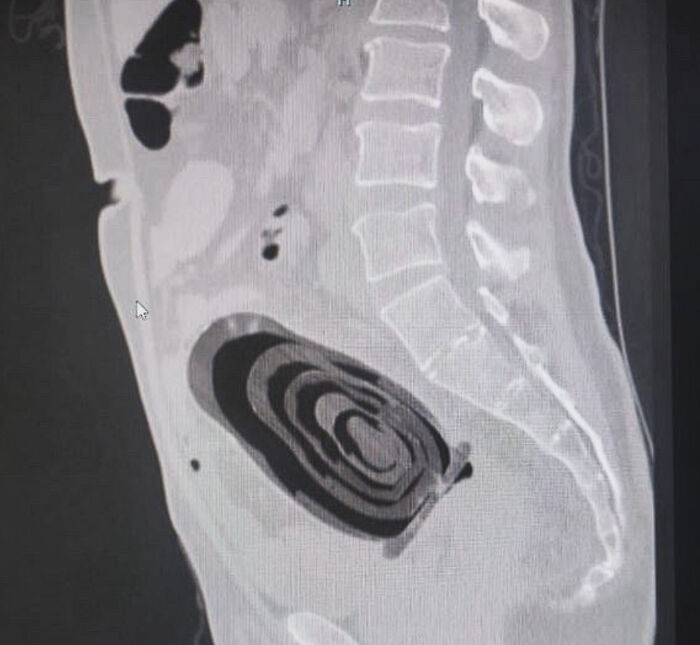

#22 A 44-Year-Old Man Arrived At The Hospital With A Strange Chest Wound. During The Examination, The Doctors Discovered That A Knife Blade Had Been Lodged In His Chest For Eight Years—without His Knowledge At All

It turns out that he was st*bbed years ago, and the wound was stitched without a deep examination. Since then, he had lived normally with no special symptoms—until the wound began to bleed, and the hidden blade was revealed in an X-ray.

The blade was surgically removed, the patient recovered, and he was discharged within a few days.